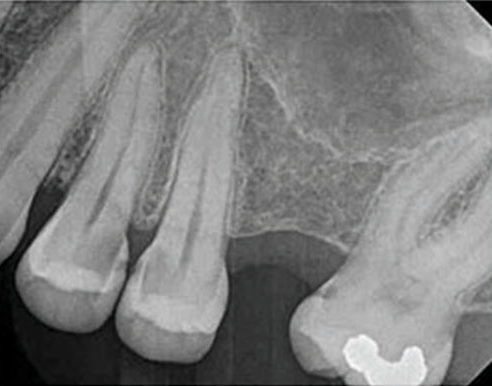

(9.) Preoperative radiograph of previously treated tooth No. 9, which received a diagnosis of acute apical abscess secondary to childhood trauma and recurrent endodontic pathology.

Figure 9

(10.) Posttreatment radiograph and cone-beam computed tomography (CBCT) scan following nonsurgical root canal re-treatment that resulted in incomplete resolution of symptoms in response to percussion and palpation.

Figure 10

(11.) Posttreatment radiograph and cone-beam computed tomography (CBCT) scan following nonsurgical root canal re-treatment that resulted in incomplete resolution of symptoms in response to percussion and palpation.

Figure 11